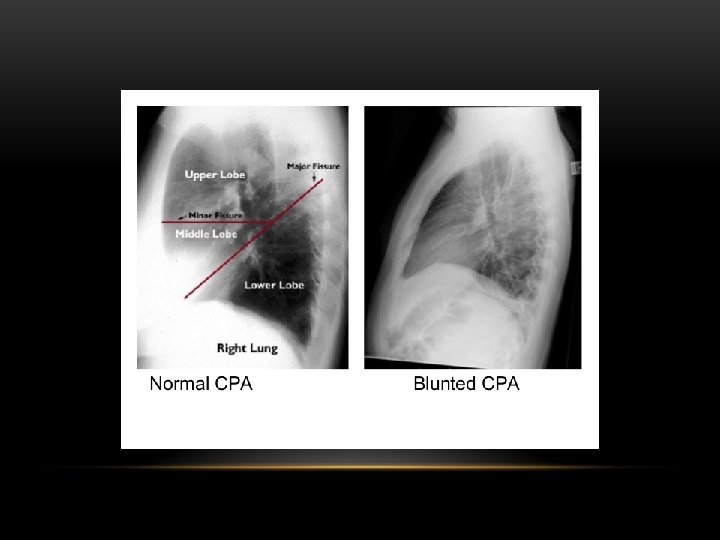

Pleural Effusion Fluid accumulates in the pleural space. Irrespective of the nature of fluid, radiologically they will look similar. Radiological criteria are: Density In dependent portion (Costophrenic angle in PA view). Blunting of costophrenic angle Lack of identifiable diaphragm (silhouette sign principle).

Causes of pleural effusion: -Infection -Subphrenic abscess. -Malignant neoplasm -Cardiac failure -Pulmonary infarction -Collagen vascular disease -Nephrotic syndrom Modalities for pl. effusion diagnosis: -Plain chest x ray. -Ultrasound -Computed tomography

Lateral Decubitus : Most sensitive, may detect as little as 25 m. L

Pleural Effusion • Homogenous density • Loss of cardiophrenic angle • Loss of diaphragmatic and right cardiac silhouette